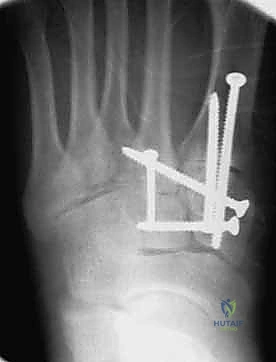

1. الرد المفتوح والتثبيت الداخلي (ORIF - Open Reduction and Internal Fixation)

هذا هو الإجراء الكلاسيكي والأكثر شيوعاً. يهدف إلى إعادة العظام إلى مكانها الطبيعي (الرد) وتثبيتها باستخدام معدات طبية (مسامير، شرائح، أو أسلاك) حتى تلتئم الأربطة والعظام.

4. التثبيت (Fixation): يتم تثبيت العظام باستخدام مسامير معدنية خاصة (Solid or Cannulated Screws) تعبر المفاصل لتثبيتها بإحكام. في بعض الحالات، يتم استخدام شرائح معدنية صغيرة للحفاظ على الاستقرار.

5. مسمار ليزفرانك: الخطوة الأهم هي وضع "مسمار ليزفرانك" (Lisfranc Screw) الذي يمر من العظم المسماري الإنسي إلى قاعدة المشط الثاني، لتعويض وظيفة الرباط الممزق.